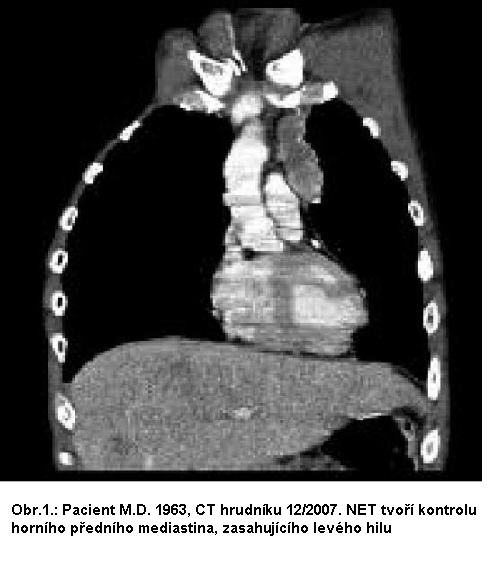

Muž, nar. 1963, s atypickým karcinoidem levého

bronchu, s metastázami do jater, uzlin a skeletu, atypickým

karcinoidovým syndromem, bolesti skeletu, flush, průjmy. V 08/2007

bronchoskopicky verifikován atypický karcinoid se střední

proliferační aktivitou (Ki67 = 20%). CT 2007: tumor obturující

lobární bronchus a stenozující levý hlavní a lobární bronchus pro

dolní lalok s meta pleury. Scintigrafie skeletu a octreoscan

pozitivní, ložiska v plicích, játrech, uzlinách a skeletu.